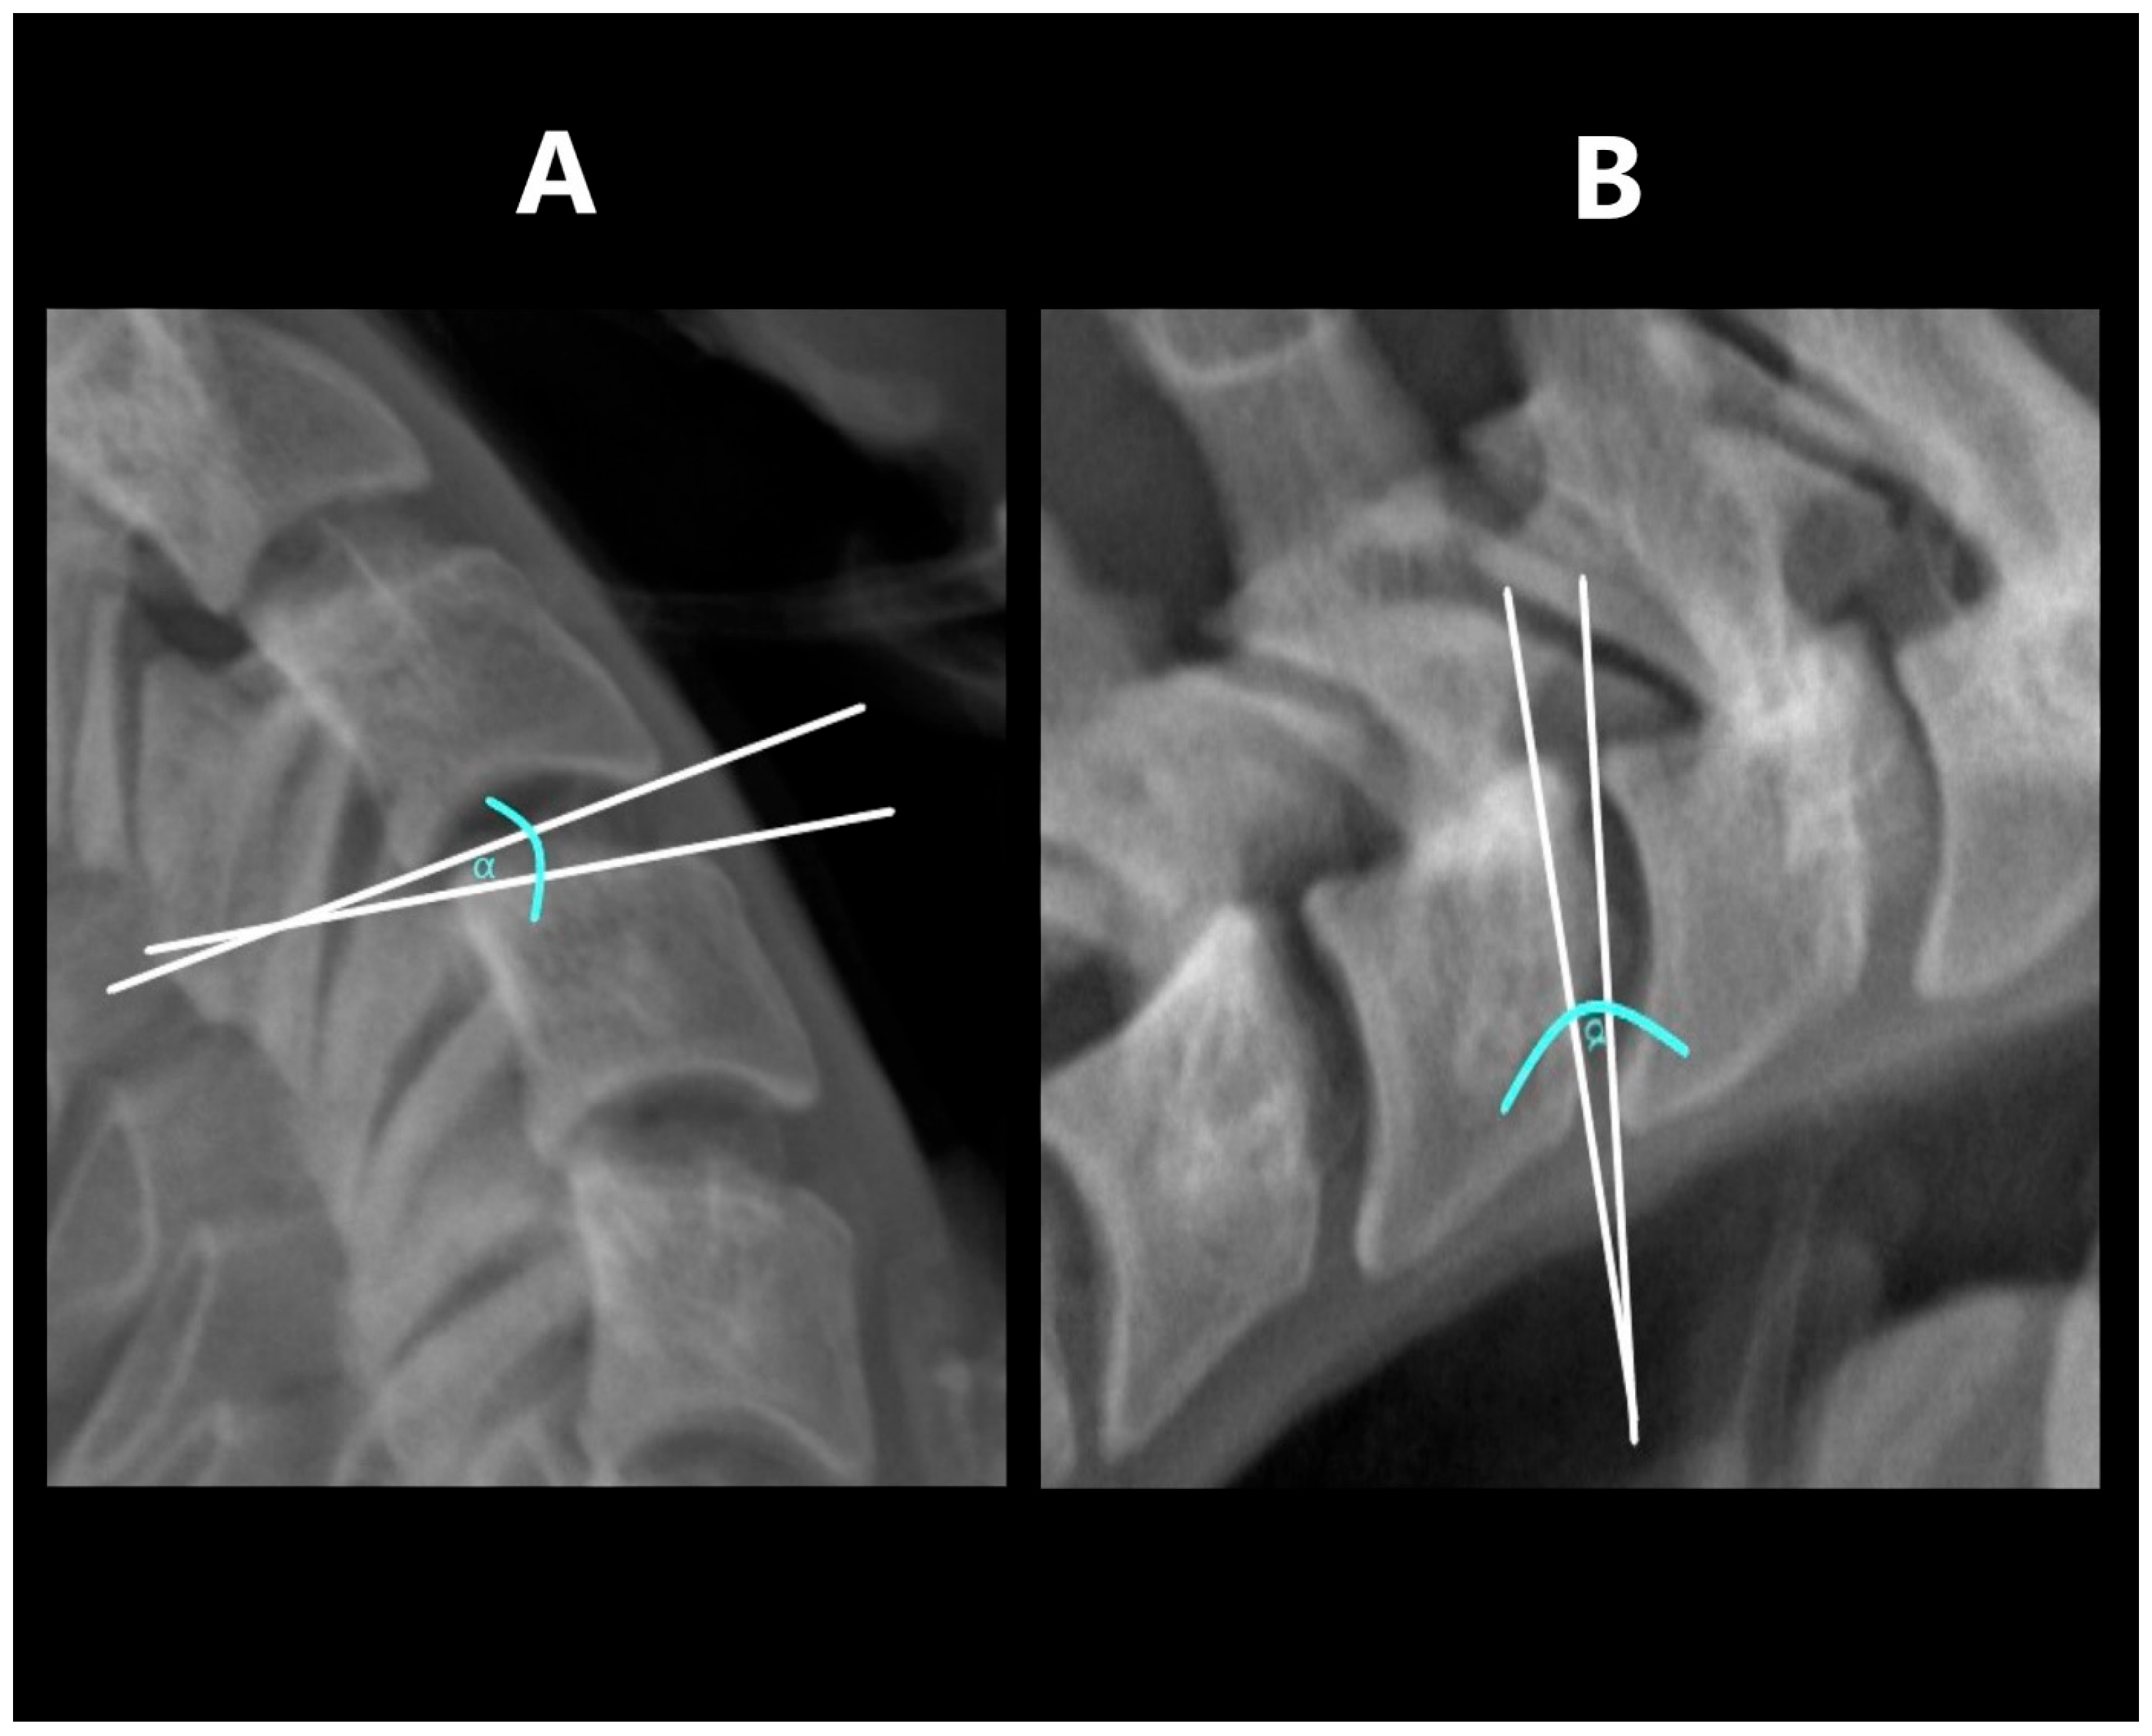

The range of horizontal segmental mobility was measured in both functional projections. This was performed by measuring the displacement of the posterior edge of the upper vertebral body in relation to the posterior edge of the lower vertebral body. In flexion projection, the upper vertebral body should shift ventrally (forward), while in the extension projection, there should be a shift dorsally (backward). The values measured in flexion and extension were then related to the width of the spinal canal at the level of the lower vertebra. Measurements were taken at the narrowest point between the posterior contour of the vertebral body and the anterior contour of the spinous process of the same vertebra [6,12] (Figure 2).

Figure 2. Measuring HDI: (A)—in extension, (B)—in flexion. Tangent lines to the posterior edge of vertebras—red lines; horizontal displacement distance—blue lines; spinal canal width—green lines.